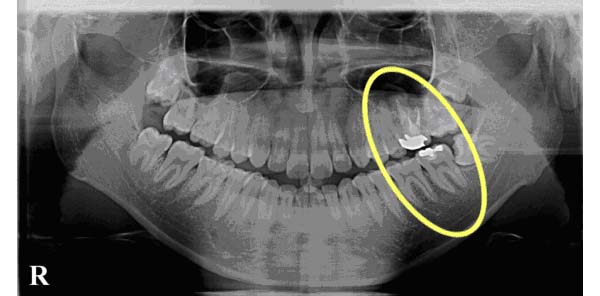

この絵はスライド写真イメージから当院スタッフ森下にかわいらしく書いてもらったイメージ図です。吉本歯科医院では「親知らずは抜歯した方がいい」とおすすめしています。他の歯にまったく影響を与えず、まっすぐすーっと親知らずが生えているならいいのですが、そのような方は10000人に数人程度です。つまり、ほとんどの方は親知らずが悪さをしているとお考え下さい。歯が後ろから倒れているようなかみ合わせになってしまっていると、噛む力は上からかかるため、下図のようにどんどん歯が傾くのに拍車がかかり、さらに後ろから前に押される力が歯にかかるため、さらさらにどんどん歯並びが崩れたり、押された歯が割れたり、つぶされたり、詰め物などが壊されたり外されたり、遠く離れた前歯まで飛び出てくるといった事が起こります。さあ、では実際に親知らずが原因で咬み合わせを破壊し、他の歯全体へ悪い影響を及ぼしている症例をご紹介しましょう。↓このレントゲン写真は吉本歯科医院で開業当時に現像していたころの写真ですので、見えにくいです(^^:)

親知らずが原因で咬み合わせを破壊している症例①

右下部分を切り出して拡大しました。

8と赤く囲んでいる部分が親知らずです。横に向いて生えていますね。親知らずの手前の歯7番目、その手前の歯6番目、どうなっているでしょう?6番目は全体写真で鼻の骨を起点にみると斜めに倒れて、かつ、上に上がっていますね。親知らずに押し上げられているんですね。神経の治療も受けられて何度も治療されています。

このレントゲン写真でもう一つ重要なことが、あります。それは、親知らずのすぐ手前の7番目の歯の根っこをご覧下さい。根の周囲が黒いですよね。歯を支えている骨が溶けているんです。

レントゲン写真というのは硬いところが白くうつります。5番目の歯の根っこのあたりは歯の根の周りがまだもや~っと白くうつっています。これは硬い「骨」が写っているんです。しかし、7番目には、骨が、ない。

さらに6番目の根っこの7番目よりのあたりまで骨が溶けています。7番目の歯を支えている骨が全然ないのです。6番目の歯を支えている骨が後ろ半分すでにないのです。ということはこの7番目の歯はグラグラに揺れています。抜かなければならないということです。ほっといてもそのうち7番目は勝手に抜けます。ほっておくと6番目も同じ運命になります。「親知らず」を抜かずに放置しておいたために、その「親知らず」が横に押し上に押し、さらにこの7番と8番の間に溜まったバイ菌が取りきれないわけです。ここはどんなにご自身で歯ブラシをしても、フロスをしてもばい菌を取りきること は出来ません。歯周病とは「歯を支えている骨が溶ける病気」です。つまりこの方は親知らずが原因で「歯周病」を引き起こしてしまっているということなのです。